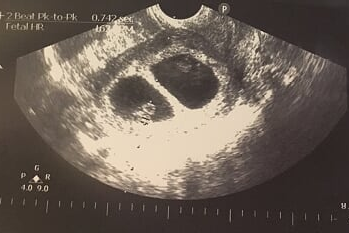

另一方面醫生發現寶寶生長嚴重落後,每隔幾天便要照超聲波,醫生告知若寶寶生長再落後或停止生長便要即時開刀,否則隨時胎停。最後35週覆診時寶寶幾乎沒有再長大,35週但寶寶身體只有31週的大小,安排第二日開刀。在手術中室中幾個婦科醫生、兒科醫生、護士、麻醉師在準備著,開刀的過程中我很緊張擔心寶寶出來時會否喊,擔心會有什麼意外。最後兩個寶寶出世,女兒只有4磅,兒子只有3磅,幾個兒科醫生即時為寶寶急救插喉,在產房只能望了一下女兒,但兒子就不能看,並即時推到嬰兒深切治療病房。